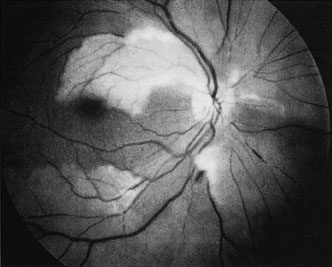

The clinical picture is typically striking. Patients present with a sudden painless loss of vision. The appearance of a cherry-red spot in the fundus is characteristic (Fig. 1).2 The cherry-red spot appears because soon after obstruction of the blood flow to the inner retina, the normally transparent retina becomes opaque and blocks the brownish-red color from the underlying choroid, which is still supplied by blood. Because the retina overlying the foveola is relatively thin, however, the normal color of the choroid is still visible in this area.3,4 Although characteristic, the cherry-red spot is not pathognomonic for central retina artery obstruction.5 Sometimes the characteristic cherry-red spot does not develop; there may be only a slight accentuation of the brownish-red color in the foveola.4 It is not known how long it takes this cherry-red spot to appear, but in a primate model, it has appeared as early as 30 minutes after obstruction.6 An afferent pupil defect is usually present.2

Fig. 1. A: Acute central retinal artery obstruction with a cherry-red spot. B and C: Intravenous fluorescein angiography. There is a delay of dye appearance in the central retinal artery, and when it does appear, it does not fill the arteries completely. D: Ocular coherence tomography (OCT) at the time of occlusion showing the increase in retinal thickness and reflectivity of the inner layers of the retina. E: Seven months later there is significant optic atrophy(G), and the OCT (F) shown now has marked thinning of the retina.

With time, the retinal opacity diminishes, generally leaving an optic nerve that is atrophic (Fig. 1). Frequently, thinned retinal arteries and veins also remain.7,8 No foveolar light reflex is evident, and a finely pigmented appearance of the macula is typical.7 In some cases, arterial collaterals develop at the optic disc.9–11 Rarely, anatomoses that exist between the central retinal artery and the ciliary arteries become visible as preretinal loops (Nettleship collaterals) after an occlusion at the edge of the disc.12,13,378In approximately 20% of patients, an embolus is evident somewhere in the arterial system.14 Emboli are discussed later.

Intravenous fluorescein angiography is useful in showing the details of the abnormal circulation of a central retinal artery obstruction (Fig. 1). The principal abnormality is the delay in the appearance of the dye in the central retinal artery and its branches.2 Rather than the central retinal artery and its branches filling rapidly, considerable time may elapse before the entire arterial system is filled.15 The filling of the retinal arteries is often abnormal, with the fluorescein partially filling an artery (a dye front) or hugging the vessel wall, as in normal venous filling.15

Optic coherence tomography (OCT) of an acute central retinal artery occlusion shows a slight increase in the thickening of the retina and reflectivity of the inner layers of the retina that correspond to the opacity seen clinically (Fig. 1).409 With time, the disc becomes atrophic and the retina thinner.